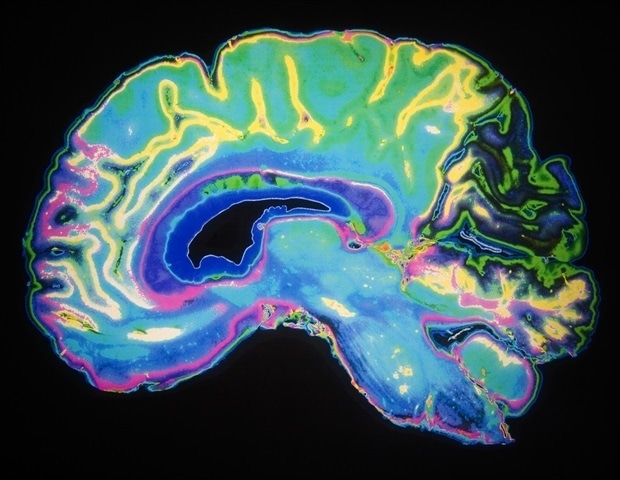

Η σκέψη μας καθορίζεται από τις γνώσεις και τα σχέδιά μας, ωστόσο η γνωστική διαδικασία μπορεί να είναι γρήγορη και ευέλικτη όταν πρόκειται για την επεξεργασία νέων πληροφοριών. Πώς προκύπτει αυτή η καλοσχεδιασμένη αλλά και ταυτόχρονα ευέλικτη φύση της σκέψης από την ανατομία του εγκεφάλου, που περιλαμβάνει δισεκατομμύρια νευρώνες και κυκλώματα; Μια νέα μελέτη από ερευνητές του Ινστιτούτου Picower για τη Μάθηση και τη Μνήμη του MIT προσφέρει νέα στοιχεία που υποδεικνύουν ότι η απάντηση μπορεί να βρίσκεται σε μια θεωρία που ονομάζεται “Χωρικός Υπολογισμός”.

Η θεωρία του χωρικού υπολογισμού, που προτάθηκε το 2023 από τον καθηγητή Earl K. Miller και τους συνεργάτες του, Mikael Lundqvist και Pawel Herman, εξηγεί πώς οι νευρώνες στον προμετωπιαίο φλοιό μπορούν να οργανώνονται αυθόρμητα σε λειτουργικές ομάδες ικανές να εκτελούν την απαιτούμενη επεξεργασία πληροφοριών για μια γνωστική εργασία. Επιπλέον, επιτρέπει στους νευρώνες να συμμετέχουν σε πολλές τέτοιες ομάδες, καθώς έχει αποδειχθεί ότι πολλοί νευρώνες του προμετωπιαίου φλοιού μπορούν να συμμετέχουν σε πολλές εργασίες ταυτόχρονα. Η βασική ιδέα της θεωρίας είναι ότι ο εγκέφαλος συγκροτεί και οργανώνει ad hoc “ομάδες εργασίας” νευρώνων χρησιμοποιώντας εγκεφαλικά κύματα συχνότητας “άλφα” και “βήτα” (περίπου 10-30 Hz) για να εφαρμόσει σήματα ελέγχου σε φυσικές περιοχές του προμετωπιαίου φλοιού.